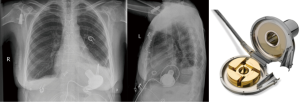

Despite promising results, the early implantable mechanical circulatory devices, which were of the pulsatile, volume displacement variety, did not have the durability required to provide ongoing, long-term support without frequent LVAD pump exchanges (5). An unacceptably high rate of device infection or malfunction requiring LVAD exchange [up to 65% by 2 years of support by one study (6)] limited widespread acceptance and use of this first generation, pulsatile LVADs. In addition, they were large, limiting their use in women, adolescents, and some men. The development of second generation continuous flow (CF), rotary pump devices [Heartware VAD (HVAD) (Figure 1), Heartmate II (Figure 2)] that were smaller, quieter, and more durable allowed for longer durations of support and the ability to implant LVADs in underserved patient populations.